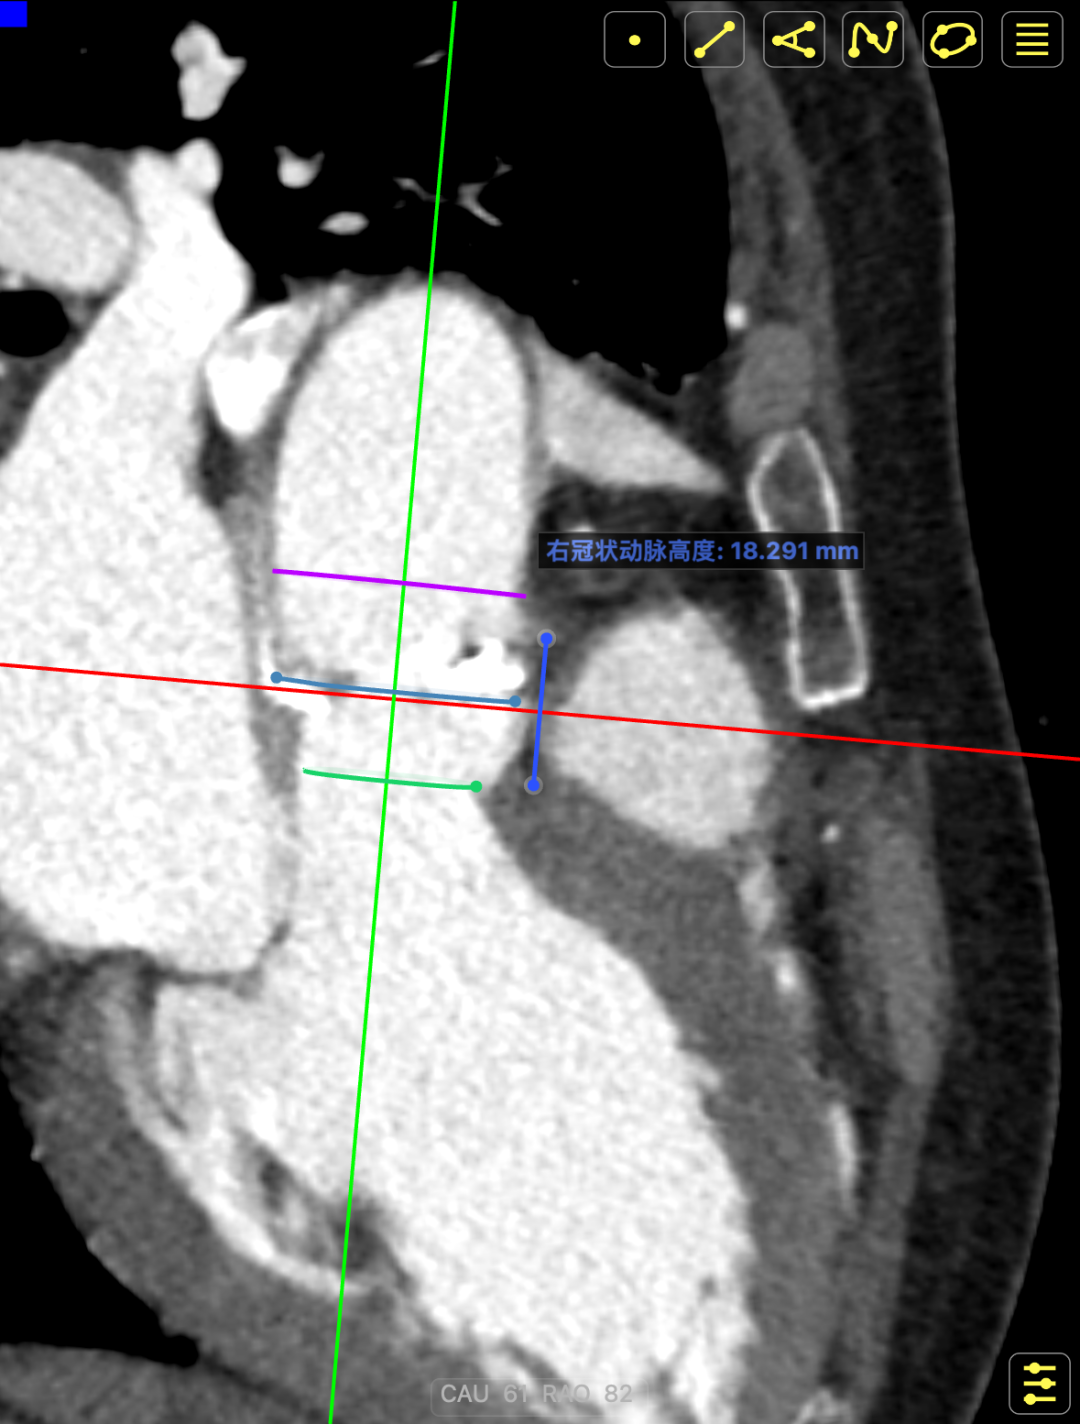

术前CT提示

主动脉瓣多发钙化,主动脉瓣为type0型二叶瓣中重度钙化。主动脉瓣环面积折算直径约24mm。患者双侧冠脉开口高度可(左冠14.46mm,右冠18.29mm),主动脉升弓降部管壁不规则并钙化斑块影,主动脉弓并龛影。升主动脉管径36mm,降主动脉管径22mm。腹主动脉、双侧髂动脉管壁不规则并可见钙化斑块影,双侧髂总动脉及其分支髂内动脉管腔轻度狭窄。

CT影像